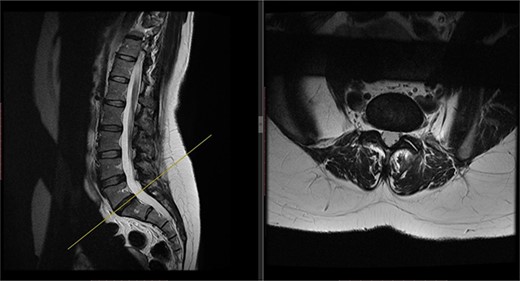

Postoperatively, the patient developed severe radiculopathy down the left leg and required opiates. The patient could not move the left leg and was unable to mobilize. X-rays showed the implants were in position (Fig. 3), but the information from a fresh MRI scan was limited due to metal artefact (Fig. 4). With ongoing, unrelenting pain, she was returned to theatre on the fourth postoperative date, and the wound was re-explored. Intraoperatively, no dural tear was identified, the nerve roots were free, and the screws appeared in position. She was then discharged home after ten nights in hospital, instead of the standard three nights that would be common practice.

Postoperative X-ray of the lumbar spine performed in January 2017, showing the implants in place.